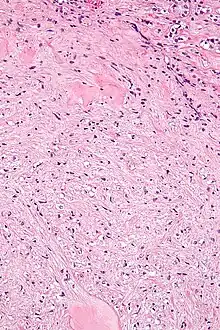

| Micrograph of a renal medullary fibroma (bottom of image). Renal tubules are seen at the top of the image. H&E stain. | |

Renal medullary fibromas are diagnosed by pathologists based on the examination of tissue.

They consist of bland spindle-shaped or stellate-shaped cells in a loose stroma. Renal tubules may be entrapped.